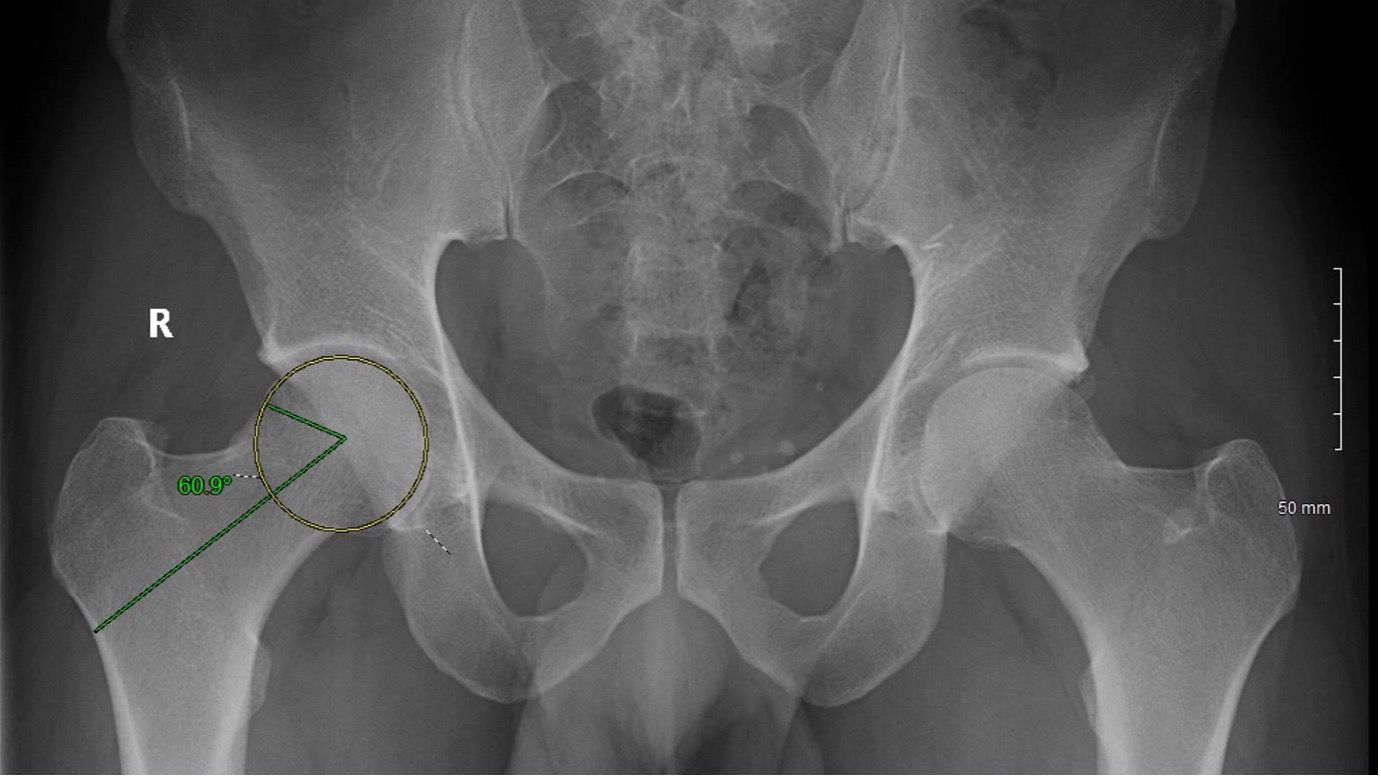

The accompanying articles span several domains of lower limb surgery. Hip preservation is addressed through current concepts in the arthroscopic management of femoroacetabular impingement, while minimally invasive arthroplasty is examined via the piriformis-preserving MIS posterior STAR approach for THA. Patellofemoral biomechanics are explored in the context of supratuberositary tibial deformational osteotomy for instability due to excessive tibial torsion. The issue is further complemented by a synthesis of the 2021 International Consensus Meeting on Venous Thromboembolism.